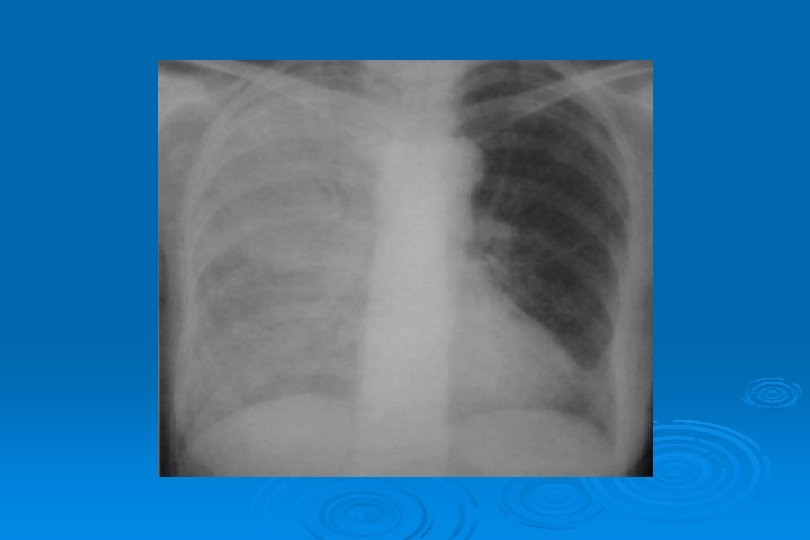

MİKOPLAZMA PNÖMONİSİ Muayenede ince-orta yaş railer duyulur. Hastalık ilerledikçe submatite ve matite alınır ve railer artarak daha kaba bir nitelik kazanır. Sibilan, ronflan railerde duyulur. Ø Radyografide; Yer yer nodüler, parçalı veya perihiler infıltrasyonlar, bazı vakalarda lober veya lobüler yoğunlaşma görülür. Ø Hastalığın ilk haftasından sonra %75 vakada kanda soğuk aglütünasyon oluşur. Soğuk aglütünasyon virüs, bakteri pnömonilerinde ve bazı kan hastalıklarında da pozitif olabilir. Mikoplasma pnömonisinde perifer ve santral nörolojik anormallikler, trombositopeni, deride eritem gibi komplikasyonlar gelişebilir. Ø Ø Hastaların %10 -20’sinde makülopapüler döküntüler vardır. Tanıda önemli bir ipucudur.

MİKOPLAZMA PNÖMONİSİ Yamalı, segmental veya lobar konsolidasyon veya buzlu cam yoğunluğu Ø İnterstisyumda kalınlaşma Ø Mozaik perfüzyon Ø

M. Pneumoniae Pnömonisi